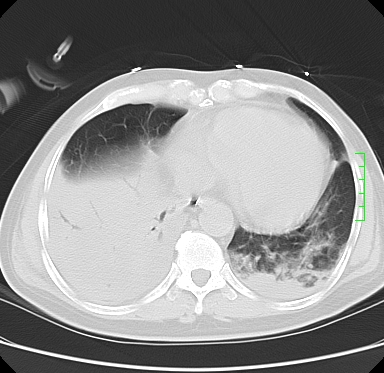

icu病人,几天都没明确诊断。m,76y,咳嗽、咳痰1周,伴气促,右胸痛入院,pe:t38.3c p135 r25 bp135/85。双肺可闻及大量湿罗音,心、腹未见明显异常。诊断:1心衰?2肺部感染?3冠心病?

11号ct

双肺感染性病变,下叶膨胀不全,胸水,左室大。

1)两肺感染性病变(右肺下叶肺脓肿可能)。2)双侧胸腔积液,以右侧为甚。

混合型肺水肿合并感染,肺膨胀不全,胸膜肥厚粘连包裹,同时肺内有陈旧性病灶。注意复查

ards,肺感染性病变,右下叶实变,双侧胸腔积液,右侧为著,叶间胸膜积液,右上肺陈旧性tb纤维灶,左室大。